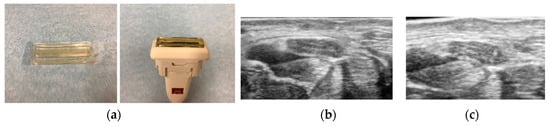

The visualization of the median nerve from proximal to distal carpal tunnel requires a high-quality ultrasound machine and good ultrasound technique to clearly determine the margin of the nerve. Clear visualization of the median nerve at middle or distal carpal tunnel is sometimes impaired by the inherent slight curvature of the palm, the thickness of the skin, subcutaneous fat, the relatively deep location, and the oblique course of the nerve. This may explain why previous studies have not fully assessed the usefulness of cross-sectional area distal to the wrist crease. One possible solution to improve image quality in this area is using an acoustic coupler for the transducer (Figure 2). This allows good adaptation of the transducer to the skin and can obtain a clear image of the median nerve. Another approach to quantifying focal nerve enlargement is the median nerve wrist-to-forearm cross-sectional area ratio, which allows a patient to serve as their own internal control. The diagnosis of CTS improved when using the wrist-to-forearm ratio as opposed to a diagnosis established only on the basis of a single measurement of the cross-sectional area at the level of the wrist [39]. In that study, the cross-sectional areas of the median nerve were measured at the wrist level and approximately 12 cm proximally from the wrist. The wrist-to-forearm ratio was 2.1 ± 0.5 in patients with CTS and 1.0 ± 0.1 in asymptomatic volunteers. A wrist-to-forearm ratio of 1.4 or more showed 100% sensitivity for detecting patients suffering from CTS. Also, it may be possible to compare the median nerve size with the healthy side if the case is unilateral. This may be a reasonable option to standardize the assessment of cross-sectional area of median nerve for CTS diagnosis.

Figure 2. Use of acoustic coupler for the uneven skin surface. (a) Acoustic coupler, (b) an example image of median nerve without acoustic coupler, (c) an example image of median nerve with acoustic coupler. Fascicular pattern can be visualized with the acoustic coupler.